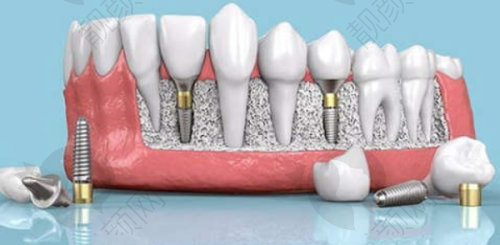

中诺口腔医院提供了丰富的单颗种植牙选择,价格因种植体品牌和材料不同而有所差异。国产种植牙价格较为亲民,像百康特种植牙 2980 元/颗起、威高种植牙 3000 元/颗起、莱顿(BLB)种植牙 3800 元/颗起。这些国产种植体性价比高,适合预算有限的患者。

韩国进口种植牙也特别受欢迎,登腾种植牙 2980 元/颗起(活动价)、奥齿泰种植牙 5000 元/颗起、沃兰种植牙 3800 元/颗起。韩国种植体在市场上应用广泛,技术成熟,质量有保护。

美国进口种植牙如皓圣种植牙 4000 元/颗起、百好瑞 Biohorizons 种植牙 6700 元/颗起;德国进口种植牙有 ICX 种植牙 4880 元/颗起、威兰德种植牙 2600 元/颗起、瑞西欧种植牙 8100 元/颗起;瑞士进口种植牙 ITI 种植牙 6000 元/颗起(常规方案)、12000 元/颗起(高端型号);瑞典进口种植牙诺贝尔种植牙 7800 元/颗起(PMC 型号)、14000 元/颗起(高端型号)。欧美进口种植体通常在质量和性能上更胜一筹,适合对种植牙品质有较高要求的患者。